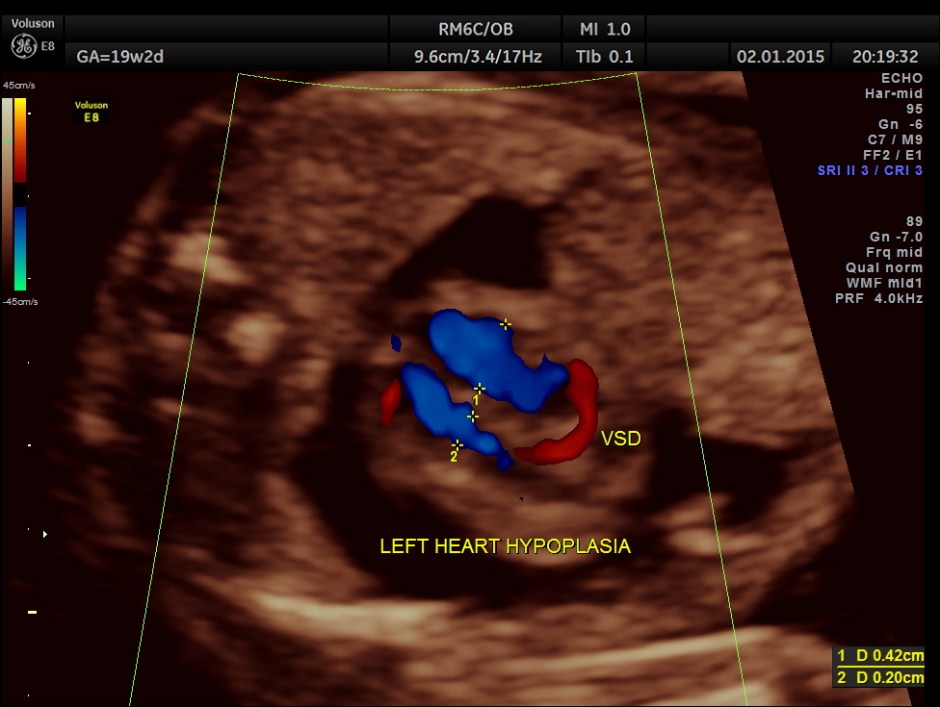

A prominent muscular ventricular septal defect is seen.

Apart from the VSD , left heart appears disproportionately smaller.

Great vessel crossing is seen.

This fetus had a large pericardial effusion with structural defect of the heart – VSD and disproportionately smaller left heart – possibly co-arctation of aorta . The patient was advised chromosomal studies and was lost for follow up.